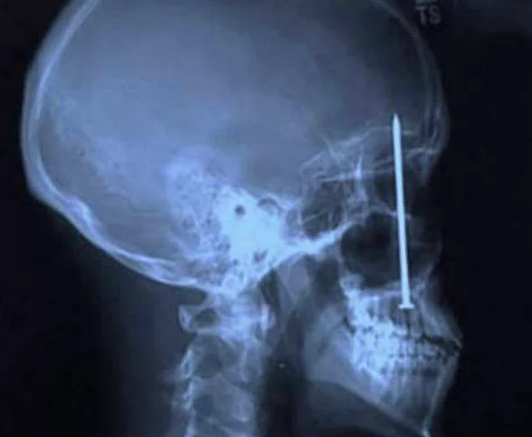

Diş Ağrısından Fazlası

Bu Xray'in sahibinin o çiviyi oraya sokmasından daha ilginci, diş ağrısı sebebiyle dişçiye gittikten sonra orada bir çivinin olduğunu farketmesi..